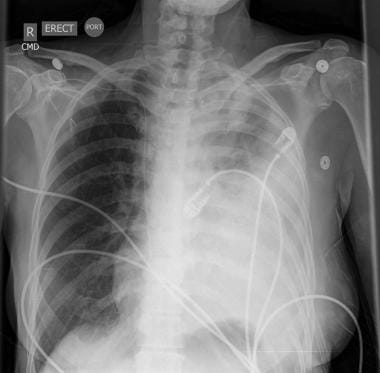

46+ Cancer Chest Catheter Images. What are catheters and ports? A central venous catheter (cvc) is a thin, flexible tube (catheter) that is placed into the large vein above the heart, usually through a vein in the neck, chest or arm.

A hickman catheter is a small, soft tube inserted in your neck or chest that hangs down outside your skin. A tunneled catheter is surgically placed into a vein in the chest or neck and then passed under the skin. Treatment may result in infertility.

A picc line (peripherally inserted central catheter) is a type of central line.

This video demonstrates the correct way to change the sterile dressing that covers the catheter. If you have a port or neck or chest catheter, your doctor or radiologist will make a small cut in the skin. What are central venous catheters? Cervical cancer is caused by the human papillomavirus (hpv).